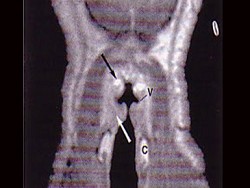

11.MRI检查结果如下图,下一步最重要的检查是  (    )